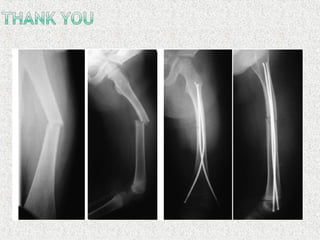

TENS